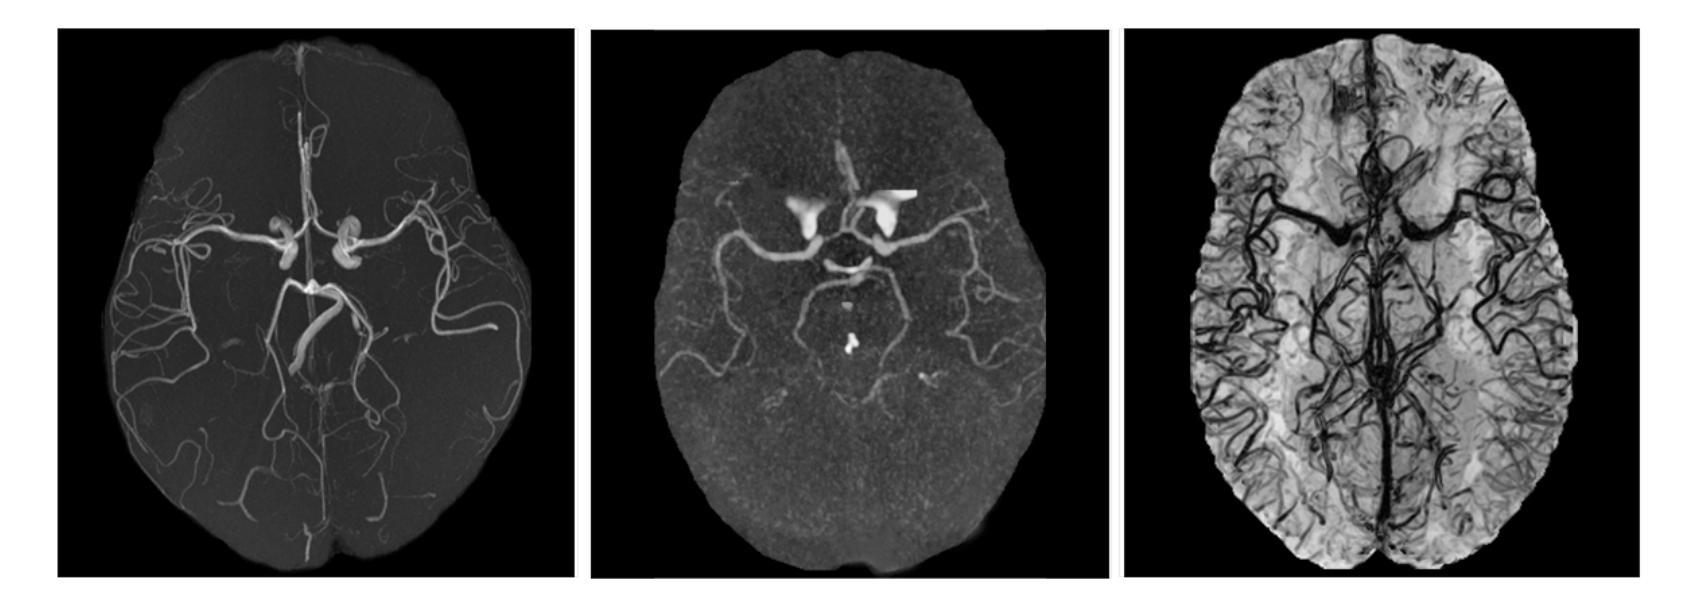

Multi-Domain Brain Vessel Segmentation Through Feature Disentanglement

The intricate morphology of brain vessels poses significant challenges for automatic segmentation models, which usually focus on a single imaging modality. However, accurately treating brain-related conditions requires a comprehensive understanding of the cerebrovascular tree, regardless of the specific acquisition procedure. Our framework effectively segments brain arteries and veins in various datasets through image-to-image translation while avoiding domain-specific model design and data harmonization between the source and the target domain. This is accomplished by employing disentanglement techniques to independently manipulate different image properties, allowing them to move from one domain to another in a label-preserving manner. Specifically, we focus on manipulating vessel appearances during adaptation while preserving spatial information, such as shapes and locations, which are crucial for correct segmentation. Our evaluation effectively bridges large and varied domain gaps across medical centers, image modalities, and vessel types. Additionally, we conduct ablation studies on the optimal number of required annotations and other architectural choices. The results highlight our framework’s robustness and versatility, demonstrating the potential of domain adaptation methodologies to perform cerebrovascular image segmentation in multiple scenarios accurately. Our code is available at https://github.com/i-vesseg/MultiVesSeg.